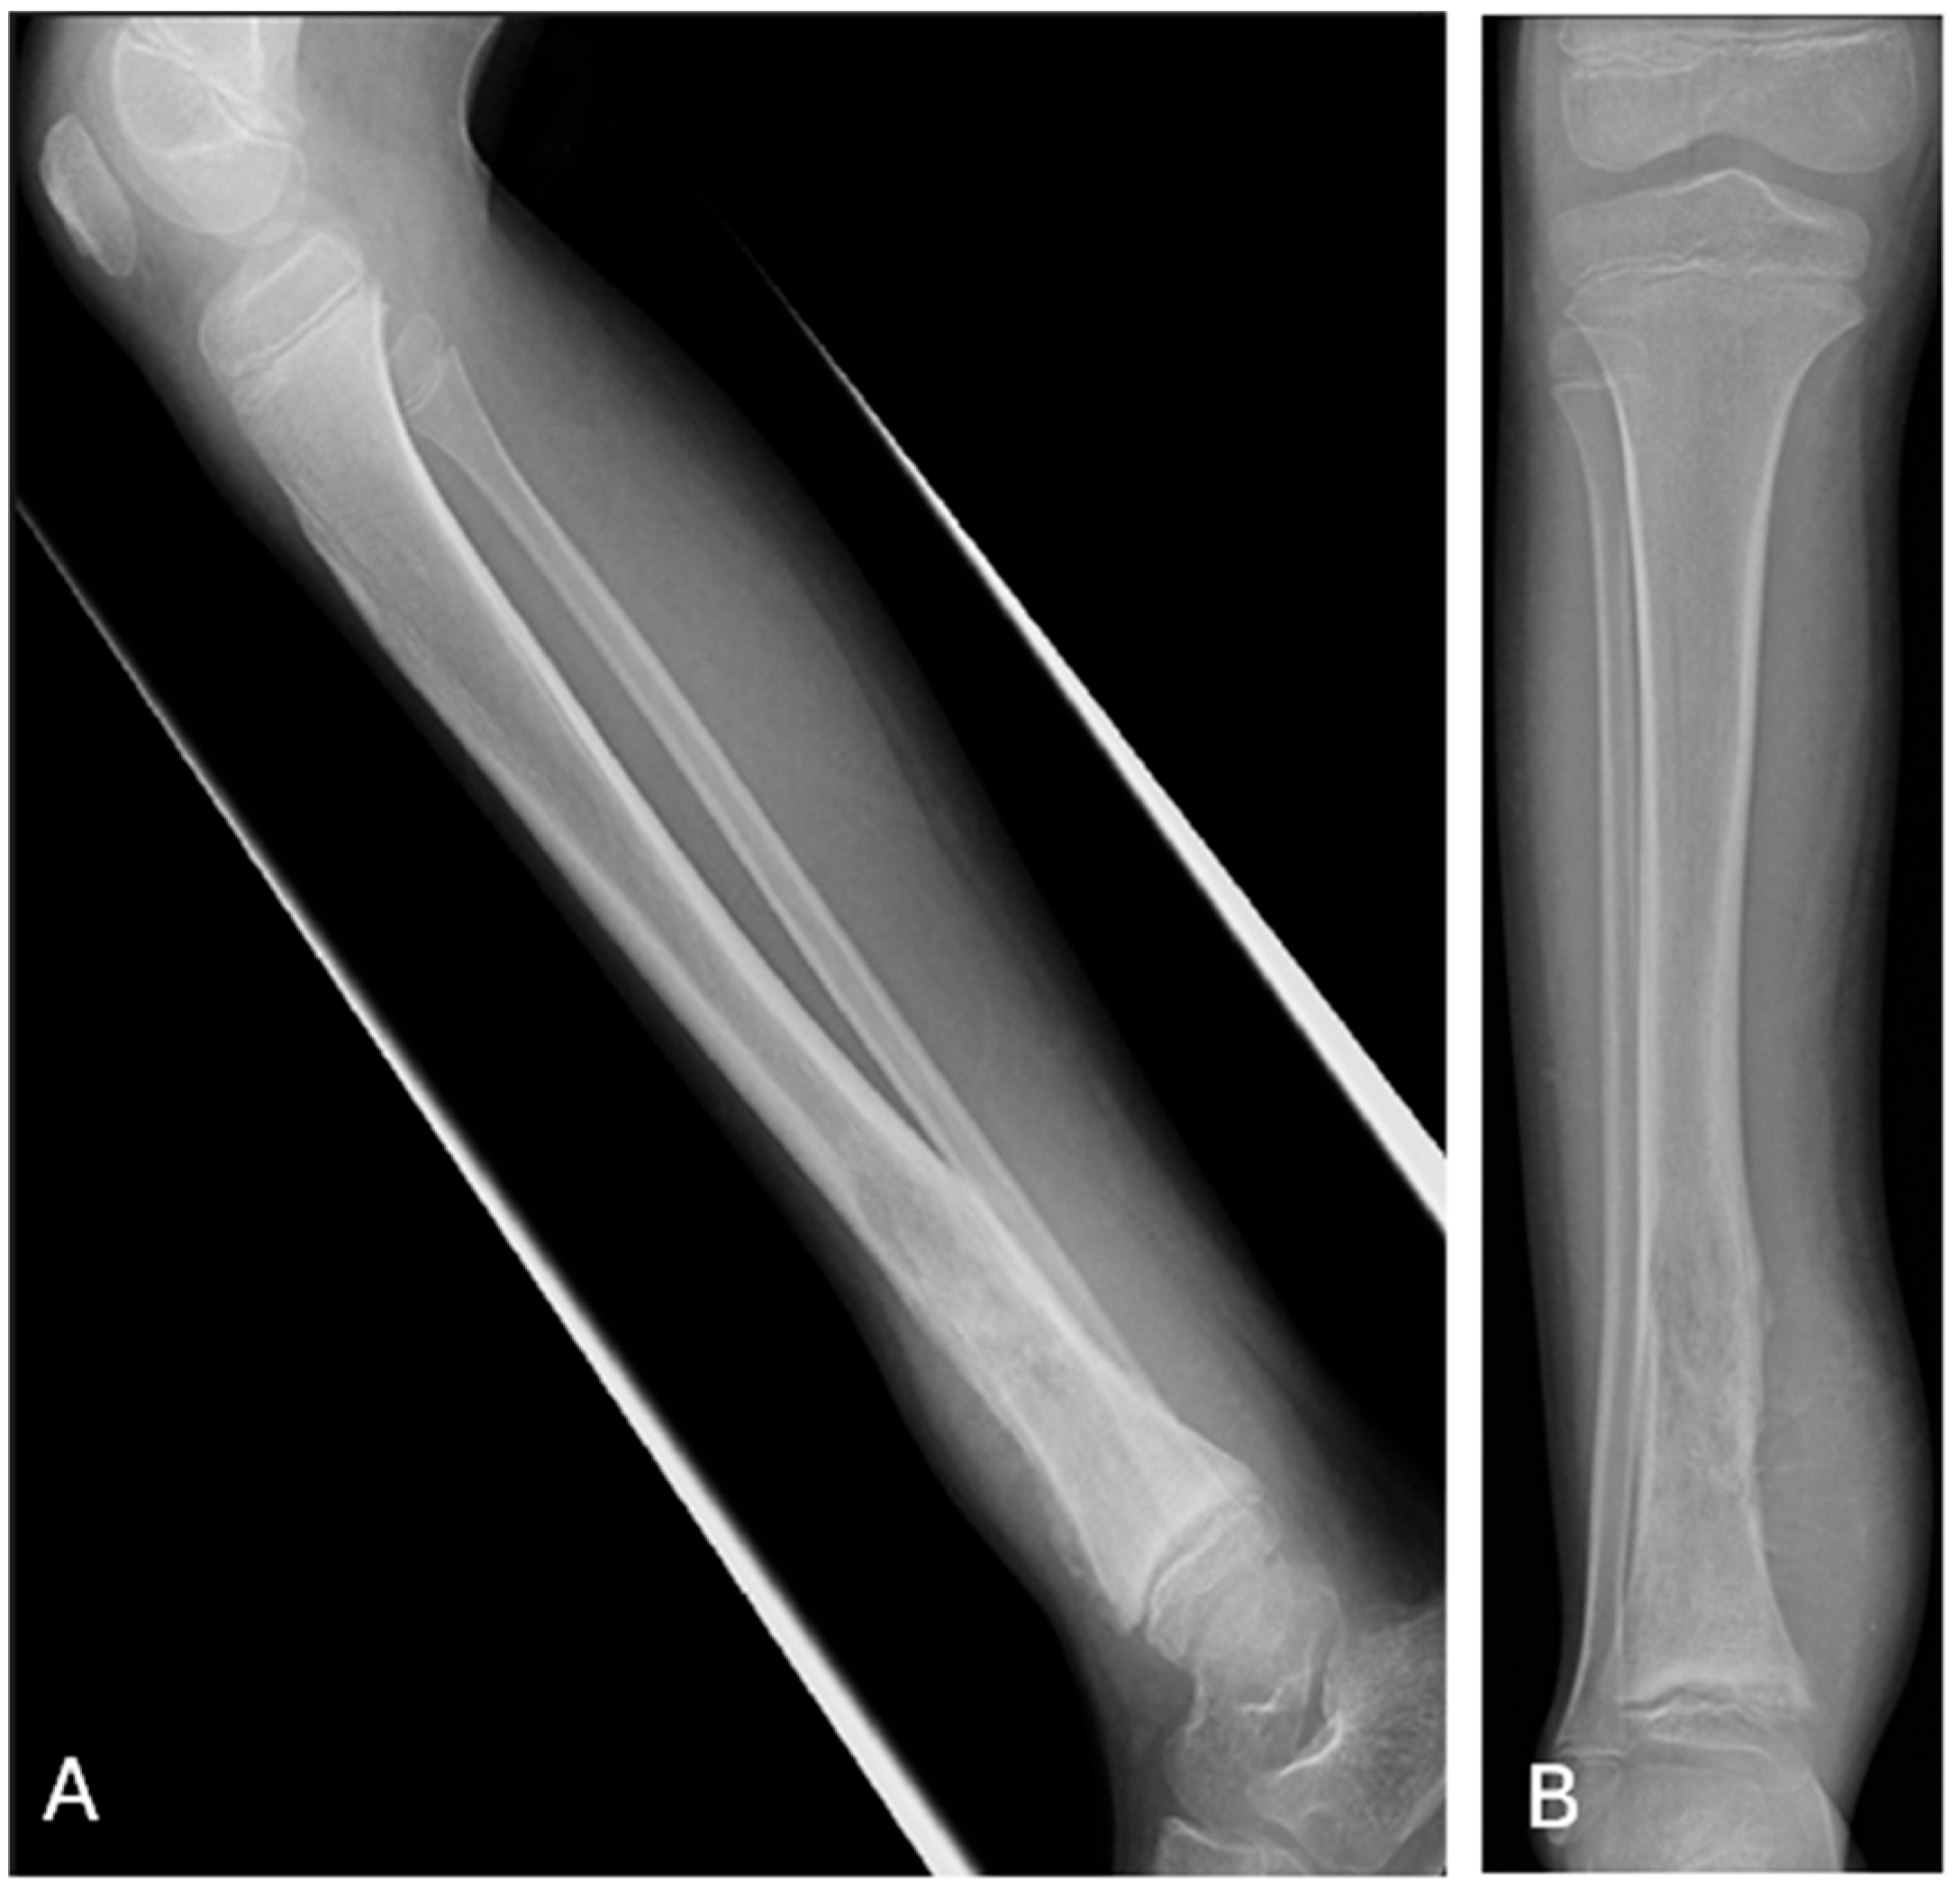

- After acquiring that initial ability to recognize that there is an imaging abnormality, the resident begins to progressively learn how to describe the finding, using the expected nomenclature. This knowledge is gained through exposure with the attending radiologist during block rotations that continue through residency and through available learning resources.

- As the resident acquires further imaging knowledge and experience, the thought and reasoning processes are focused on advancing their perceptual and descriptive skills to include significant associated ‘positive’ imaging findings, supporting the diagnosis they now have in their mental knowledge bank and are considering in that particular case.

- With ongoing exposure to varying disease processes, associated imaging and an advancing imaging knowledge base, the progressing resident learns to recognize the value of significant ‘negative’ findings on the imaging study, which can help lead to a more useful consultative report and accurate diagnosis, in order to better guide patient management.